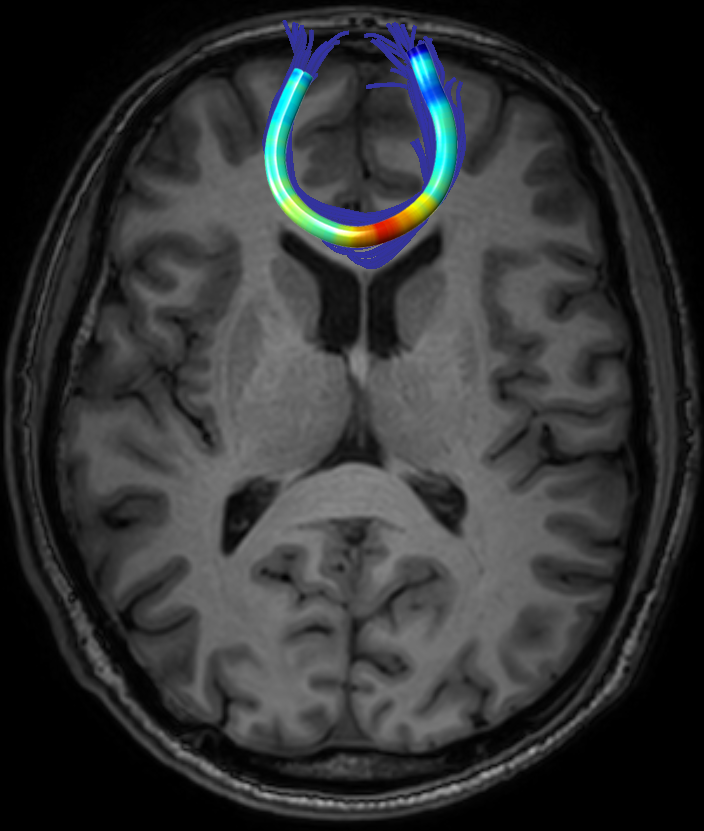

We performed pairwise comparison between two scans of a 32-year-old basketball player, diagnosed with mild occipital traumatic brain injury and frontal hemorrhage due to contrecoup impact, acquired one week and 6 months post-injury. The hemorrhagic lesion at the frontal right hemisphere of the player is no longer visible in the FLAIR image acquired 6 months after injury (Fig. 2a). Local differences between corresponding, longitudinal FA- and MD-FFDD profiles of the FMT (chosen due to its proximity to the lesion area) are shown in Fig. 2d. Figs. 2b-c present color-coded FMT to visually demonstrate these differences. Results show significant longitudinal variability at the right hemisphere part of the tract, corresponding to the lesion area, and relatively minor differences along the rest of the tract. These results should be considered as a proof of concept, validating the FFDD analysis results for the detection and localization of mTBI-related variabilities between fiber bundles.

| (a) FLAIR | (b) FA-FFDD | (c) MD-FFDD | (d) Local Differences |